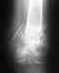

Возможно я плохо изложила свою проблему.У меня был перелом обеих костей голени со смещением. 13 января был установлен штифт.Операция была не совсем удачная т.к.сильно выступает острый обломок б.берцовой кости. Очень некрасиво и есть опасность разрыва кожи.

Три ортопеда к которым я обращалась за консультацией считают, что такой результат неприемлем. необходимо извлечь штифт и установить аппарат Илизарова.

Посмотрите снимок.Можно ли оставить всё в таком виде и впоследствии подкорректировать?